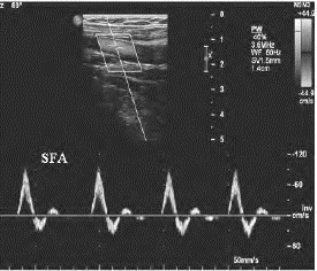

1.26.4四、动脉闭塞性疾病

1.26.10十、盗血综合征